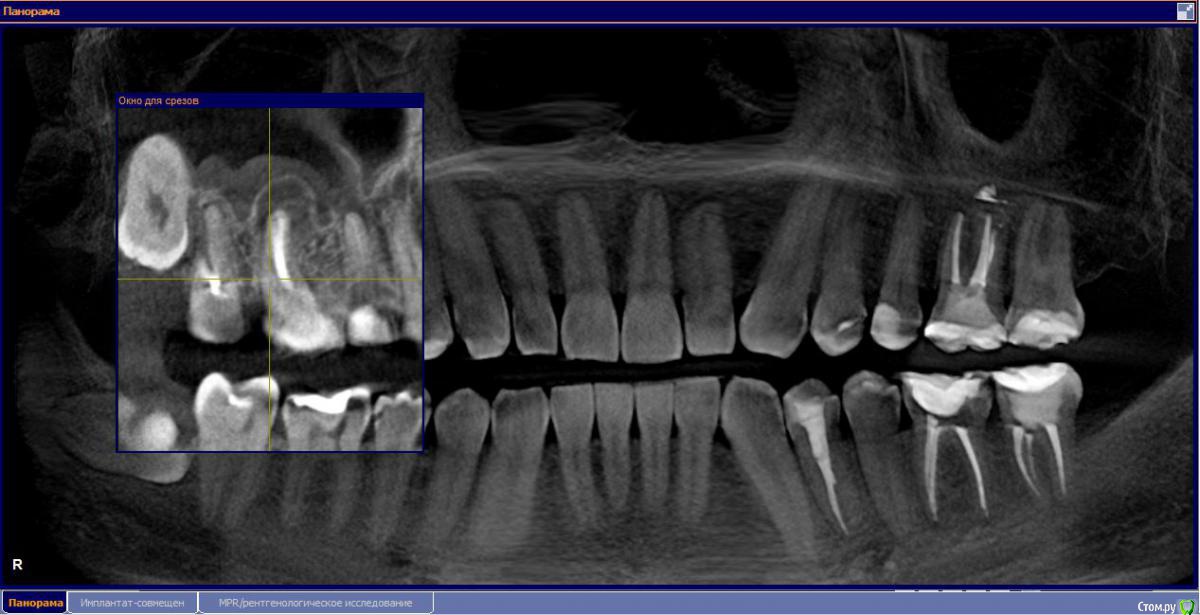

М, 33 года. Есть показания к одновременному удалению 16-го зуба - киста, и 17-го - разрушена верхушка. 8-й предлагают оставить, чтобы "держал кость" (как то так мне озвучили).

Через 3-4 месяца рекомендуют синус-лифтинг и установку двух имплантатов.

- Возможно ли консервативное перелечивание 16 зуба и есть ли смысл?

- Насколько опасная имеется киста?

снимки прилагаю.

и 6 и 7й зубы не выглядят 100% кандидатами на удаление.

1.6 большая вероятность сохранить,но понятнее при очном осмотре и диагностическом вскрытии. 1.7,скорее всего,не жилец,но тоже очно взглянуть на него стОит